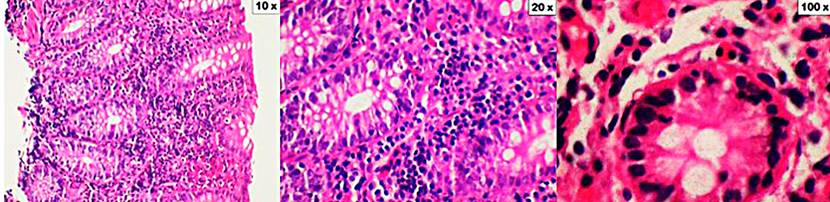

Figure 2 Lymphocytic colitis. The cuts show the mucosa of the colon distorted by a significant increase in intraepithelial lymphocytes (10x increase). In addition, there is a dense inflammatory infiltrate in the lamina propria consisting of lymphocytes, plasma cells, eosinophils, and occasional neutrophils (an increase of 20x and 100x). Coloration of hematoxylin and eosin (H&E).